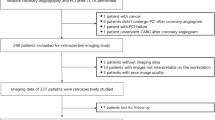

In this retrospective propensity-matched study, the Radiological Information System of our institute was queried for cardiac CT exams between September 2015 to August 2018. The subject selection and propensity score matching process is summarized in Fig. 1. During this time, 4188 subjects receiving CAC CT scans were recorded. Among these, 1181 subjects were symptomatic, and 3007 were asymptomatic. Of the 3007 asymptomatic subjects who received a CAC scan as part of a voluntary cardiac healthcare program, 27 received elective percutaneous coronary intervention afterward and were excluded. From the 1181 symptomatic group, 119 patients ultimately developed ACS. Of the 119 patients, 34 had previously received the percutaneous coronary intervention and were excluded. Six patients with no CAC and 2 CT scans with poor image quality due to severe motion artifacts were excluded. 77 ACS patients and 2980 asymptomatic subjects were enrolled for the case-control propensity score matching. Parameters for propensity score matching included the traditional risk factors of ACS, i.e., age, sex, body mass index, smoking status, diabetes, hypertension, dyslipidemia, family history of ACS[8], and CAC burden using 3 AS ranks (1-100, 101–400, and > 400). The enrolled 77 ACS patients were 1:2 propensity score-matched with 154 asymptomatic subjects as the control group. A separate cohort of 10 ACS patients was enrolled later, and we performed a 1:2 propensity score match for 20 asymptomatic subjects to form the validation cohort.